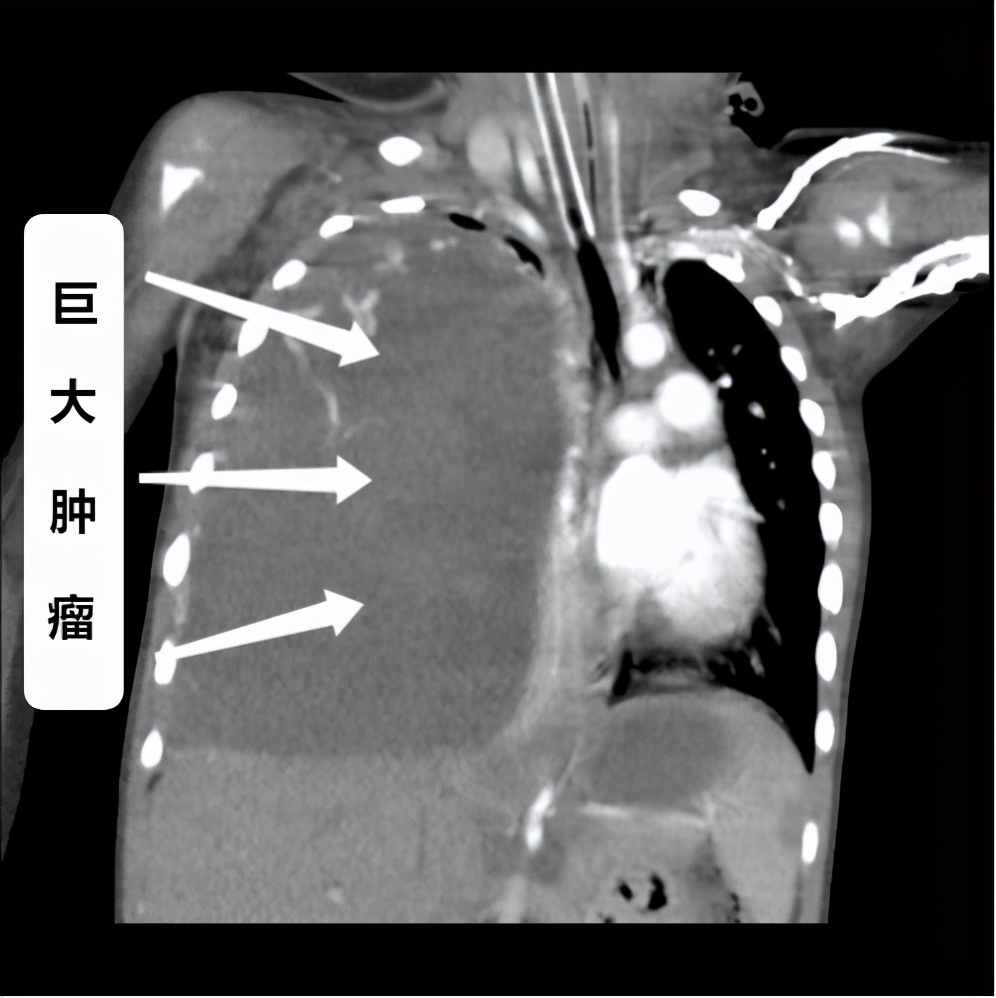

经过CT等详细检查,医生发现了欢欢体内的巨大肿瘤,判断欢欢可能患上了胸膜肺母细胞瘤并伴有脓毒血症、重症肺炎等疾病,病情危重,孩子命悬一线!

欢欢的CT提示胸腔巨大肿瘤